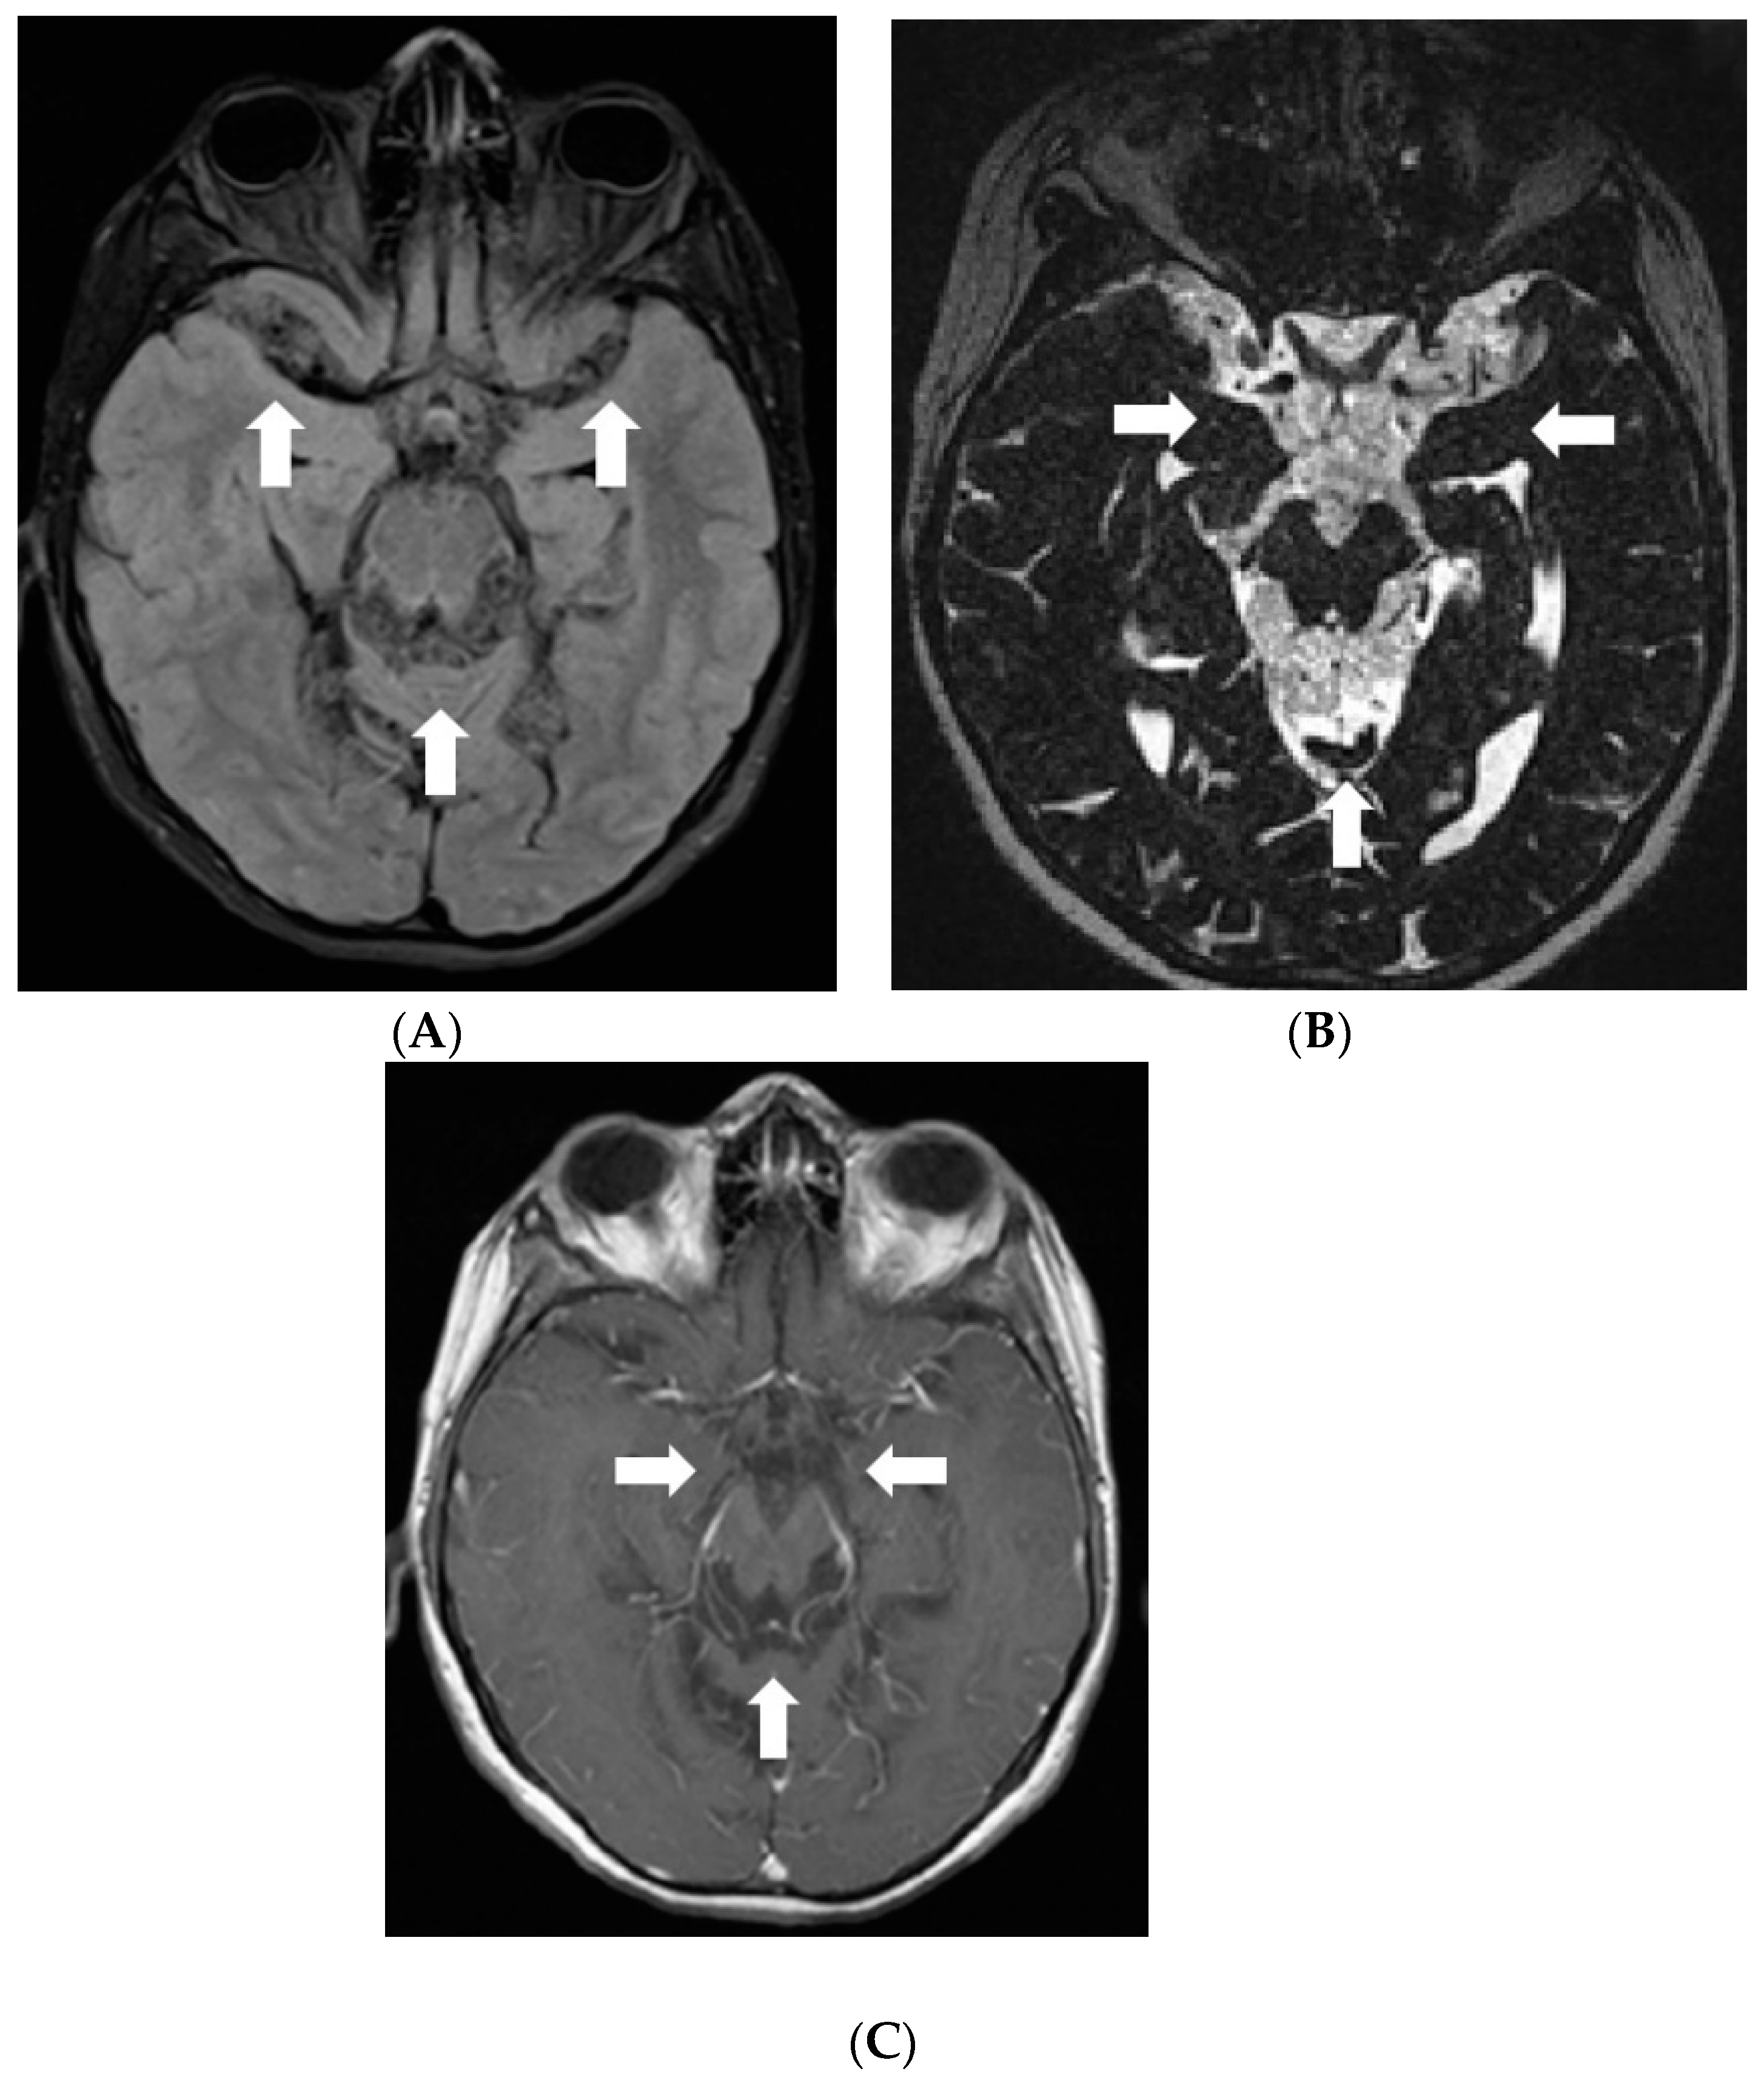

In 2017, follow-up brain MRI scans showed decreased leptomeningeal enhancement and slight decrease in size of cystic lesions in the brain; although, atrophy of the brainstem and cerebellum had progressed. However, spread of the tumour was found in the spinal canal through all its length manifested by diffuse meningeal enhancement and multiple cystic intra- and extradural lesions causing compression of the spinal cord. The girl received radiotherapy to the whole spinal cord; however, masses in the spinal canal progressed (Figure 5). In 2018, right-sided facial reconstructive surgery with medial cantopexy was performed.

Figure 5.

MRI of the spinal cord 6 years after the onset of symptoms: (A,D) Sagittal T2W, (B,E) T1W postcontrast images of the cervical and the upper thoracic spine, (C,F) postcontrast images of the middle/lower thoracic and the lumbar spine. In May 2017, (A–C) multiple confluent cystic extramedullary masses were found in the spinal canal through all its length, compressing the spinal cord at the level from C6 to T9 vertebrae. There was some nodular contrast-enhancement in the tumourous masses and diffuse meningeal enhancement. After radiotherapy in December 2017 follow-up MRI (D–F) demonstrated enlargement of the extramedullary masses in the lower cervical-upper thoracic spine with more vivid and diffuse enhancement, also, more vivid diffuse meningeal enhancement.